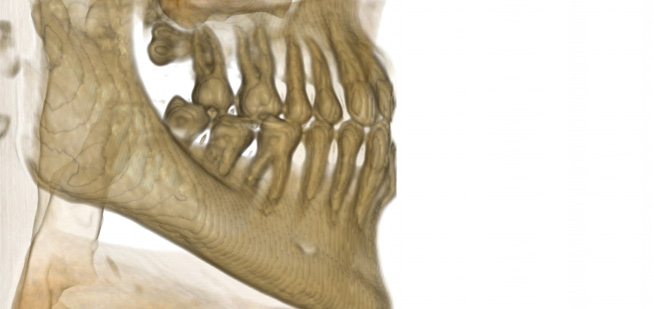

Endo-Perio

Der Facharzt für Endodontie und Periodontologie benötigt Bilder von absoluter Spitzenqualität und Detailschärfe, um Verfahren wie die Behandlung von Zahnbrüchen, die Heilung von Zahngewebe und die Therapie des Kieferkanals vorzunehmen, da er über genaue Details der behandelten Zone und des Krankheitsbilds verfügen muss, um eine wirkungsvolle Behandlung planen zu können. Nur eine eingehende Untersuchung der betroffenen Areale kann Aufschluss über einen mehr oder weniger invasiven Eingriff geben.